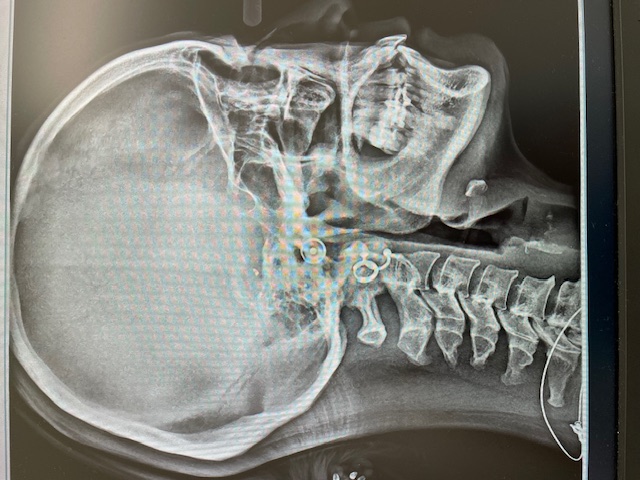

セファロレントゲン

頭の全体を横向きや正面から撮影し、顔の骨格や顎の大きさ、位置、歯の角度等を確認できます。